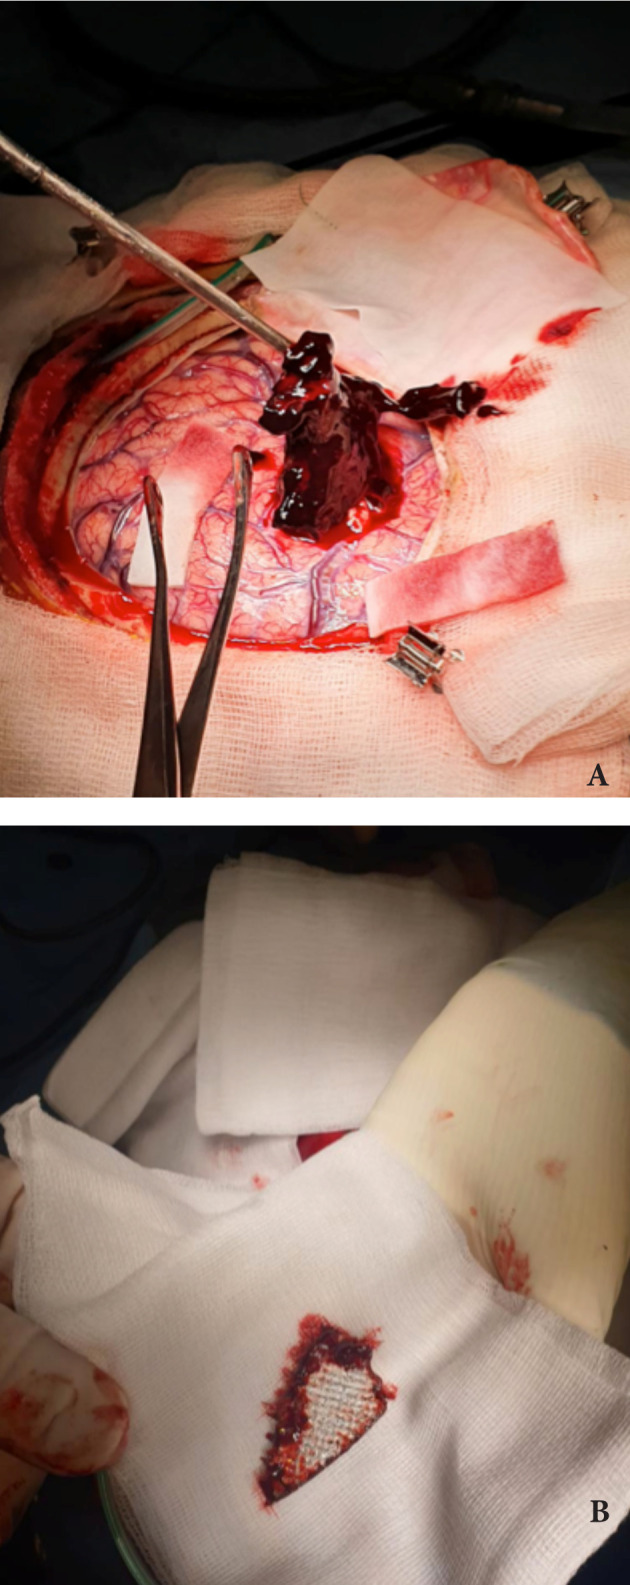

病人立即被送进手术室,接受神经外科和眼科联合手术治疗。紧急实施了左侧额颞顶骨大骨瓣减压术。彻底检查进入颅底的左侧经眶穿透伤口,用盐溶液冲洗,清除伤口碎片和源于眶顶粉碎性骨折的微小骨颗粒,以及颅内残留的微小金属异物。图4显示了眼科医生修复前的原发性左眼球损伤。手指触诊发现位于左顶叶皮质下存在一个40.0×3.2毫米(圆锯的一片)的大而尖的三角形金属异物,边缘粗糙破碎。它在直接观察下被成功移除,皮质损伤和出血最小(图5 a,b)。实现了精确的止血,将硬脑膜悬吊并敞开,放置硬膜外真空引流管,并在各层上闭合伤口。先前已经进行了伤口清创。

图4、修复之前的左眼球损伤

图5、成功取出左侧顶叶皮质下异物(白色箭头)(a)。一个尖锐粗糙的三角形金属物体被移除(b)